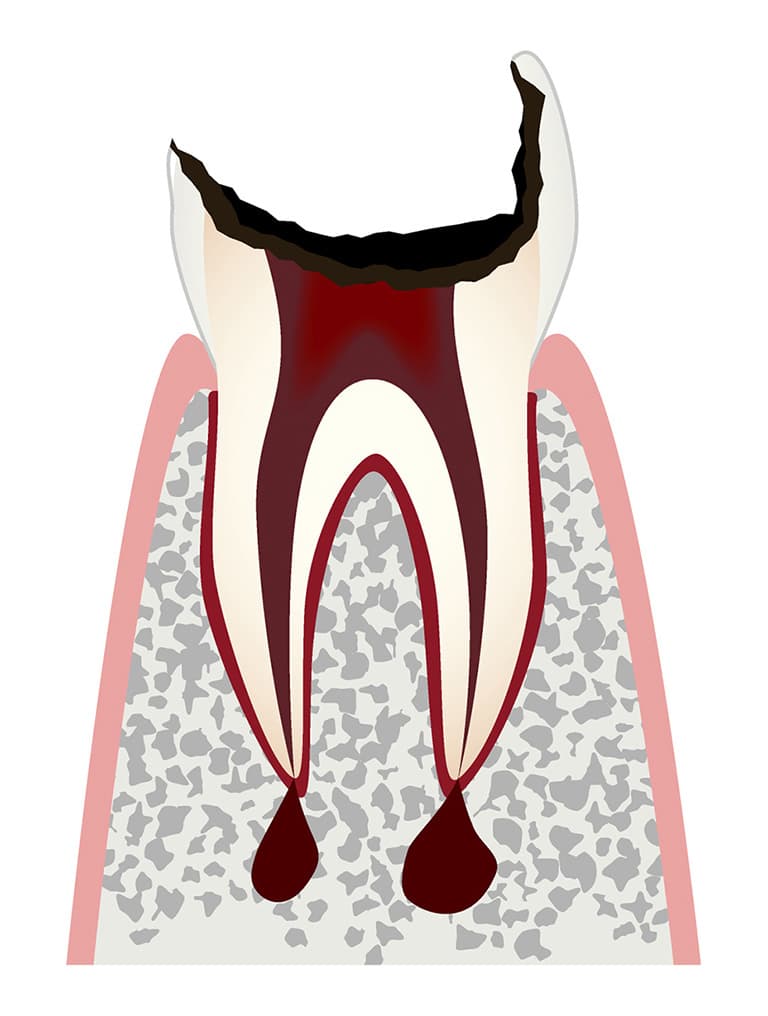

C4虫歯がかなり進行し歯の根っこだけが残った状態

虫歯がさらに進行し、歯の頭の部分がなくなり根っこだけになった状態です。

この状態まで進行すると、歯の神経があった部分(部屋)に感染を起こして根っこの先に膿をためることもあります。

痛みを感じる程度は状態によります。歯茎に膨らみや、にきびのようなできものができることもあります。

麻酔が効きにくい場合もでてくるので、早めの治療が必要です。

歯の神経まで達した虫歯を放置すると、神経が入っていた部屋(根管)まで感染を起こし、膿が根の先にたまりあごの骨の中まで広がります。

あごの骨まで膿がたまると、取り除くために歯ぐきを切開する外科手術が必要となる場合があります。